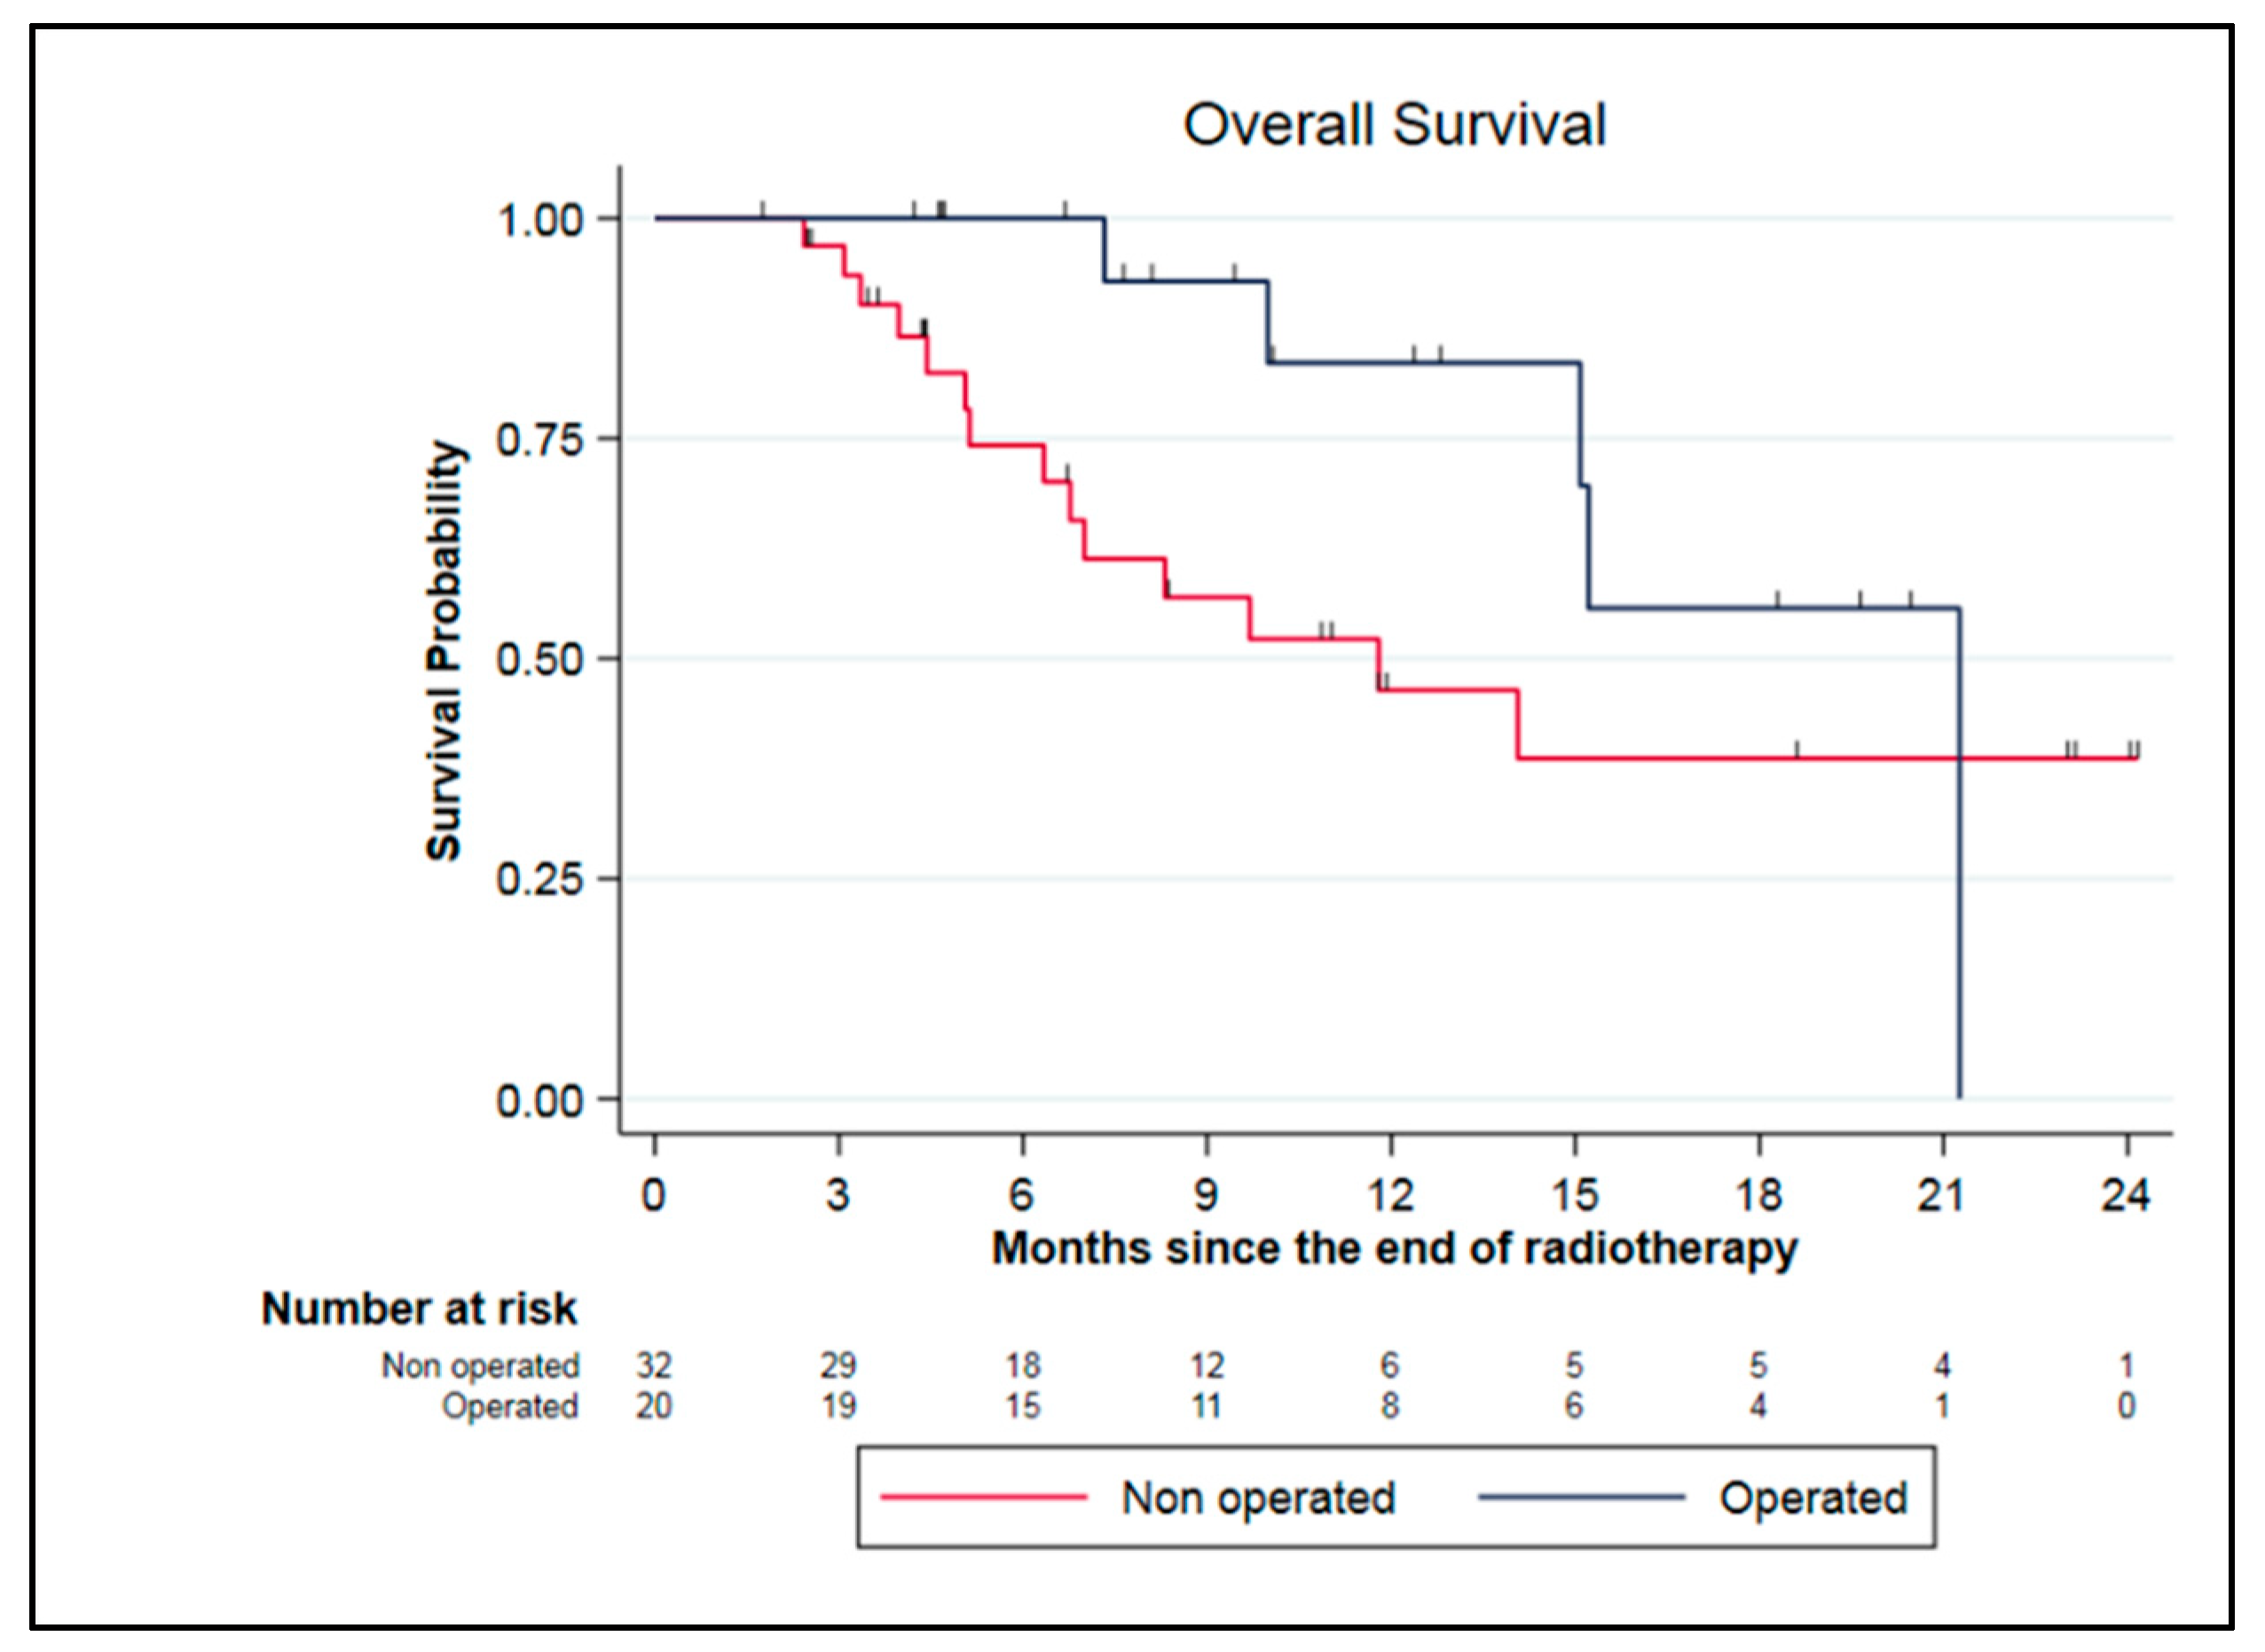

3.5. Survival Analysis

3.5.1. Whole Cohort (70 Patients)

3.5.2. LAPC and BRPC Patients (52 Patients)